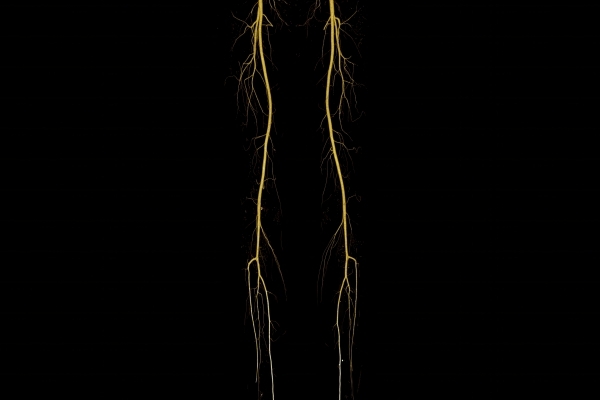

Modernste Bildgebung für jeden Bereich Ihres Körpers

Entdecken Sie, welche CT- und MRT-Untersuchungen in unserer Radiologie für jeden Bereich Ihres Körpers möglich sind.

• Gefäßdiagnostik (CT-Angiographie)

Wir bieten ein breites Spektrum an Untersuchungen an, von Standarduntersuchungen der Gelenke, Organe oder großflächigen Körperregionen bis zu Spezialuntersuchungen zum Beispiel des Herzen oder der Gefäße. Zusätzlich werden Angiographien (Darstellung von Blutgefäßen), Endometriose-Abklärungen und Mamma-Untersuchungen durchgeführt. Genauere Details können Sie der MRT/CT-Übersicht und der Preisliste entnehmen, oder Sie wenden sich direkt an unser Team, das Sie gerne zur passenden Untersuchung berät.

Ja, unsere Radiologie bietet auch Sonographie- (Ultraschall-)Untersuchungen an. Untersucht werden unter anderem Abdomen, Becken, Leiste, Brust, Venen und Gefäßen.